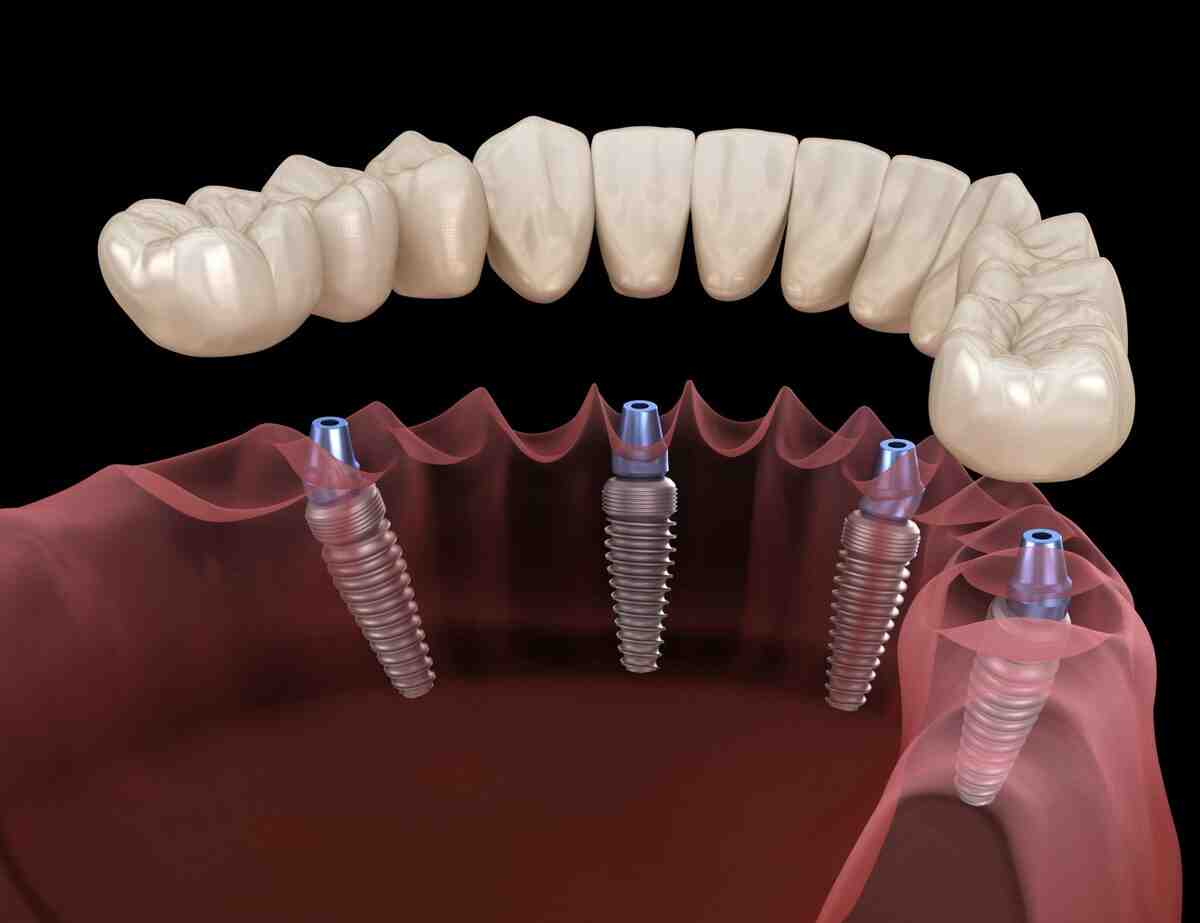

What is the cost of all on 4 dental implants

Are all on 4 implants permanent?

All-on-4 dental implants should be a permanent dental solution. With proper care, your implants can last for 20 years or more.

What are the problems with all on 4 dental implants?

Implant placement plays an important role in the restoration of ALL ON 4 and the final durability of the prosthesis. Unsupported teeth outside the implant can break due to excessive stress. To see also : Fake Teeth Options. Too much stress on implants due to poor treatment planning can lead to bone loss and implant failure.

Is all on 4 implants good?

Minimal work, maximum results. But dental implants are a situation where sometimes it is really better. While All on 4 implants are an amazing tool for many people, restoring the entire arch of a tooth to 4 implants is not an “go to” full arch implant option.